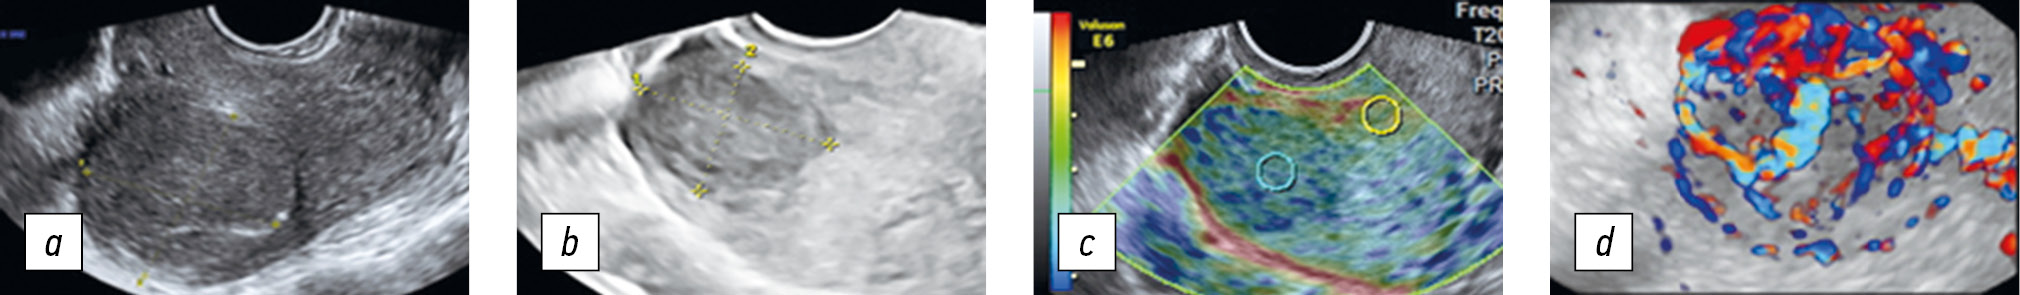

Рис. 7. Последовательное применение комплексной методики дифференциальной диагностики миомы матки и узла аденомиоза (диагностирован узел аденомиоза): а — в двухмерном режиме размер образования 20 × 19 мм; b — в трехмерном режиме образование без четких границ, размер образования 21 × 20 мм; c — эластограмма типа 2б; d — трехмерная реконструкция в режиме энергетического допплеровского кодирования с использованием методики glass body

Fig. 7. Consistent application of the complex technique for the differential diagnosis of uterine fibroids and adenomyosis node (adenomyosis node): a, 2D mode, the formation size is 23 × 19 mm; b, 3D mode, a formation without clear boundaries, the formation size is 21 × 20 mm; c, elastogram, type 2b; d, 3D power Doppler glass body